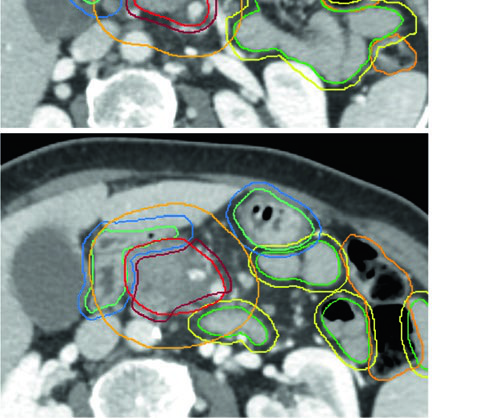

Restricciones de dosis para órganos en riesgo

Las restricciones de dosis varían según el esquema de fraccionamiento. La tabla siguiente resume los límites más relevantes para los principales OARs en la planificación pancreática, organizados por número de fracciones. La distinción entre Límite (L — nunca superar) y Guideline (G — restricción sugerida cuando la cobertura no se compromete) resulta clave para la optimización del plan.

Integración práctica: del diagnóstico al plan final

La selección del fraccionamiento en cáncer pancreático nunca es puramente académica. Tres factores determinan el esquema óptimo: la intención de tratamiento (preoperatorio, adyuvante o definitivo), la tecnología disponible (gating, CBCT, fiduciales) y la anatomía específica del paciente — en particular, la extensión de la interfaz tumor-OAR.

En la práctica, el flujo de trabajo comienza con la evaluación de resecabilidad. Los tumores borderline reciben esquemas de dosis más baja (25–50,4 Gy) con márgenes CTV generosos de al menos 1 cm y cobertura de cadenas vasculares. Los tumores irresecables son candidatos a dosis ablativa (BED₁₀ ≥ 100 Gy), pero la viabilidad depende directamente de la capacidad de excluir OARs del PTV de alta dosis con márgenes de seguridad adecuados. El escenario adyuvante, sin GTV a delinear, sigue el atlas estandarizado del RTOG 0848 con sus expansiones específicas por ROI.